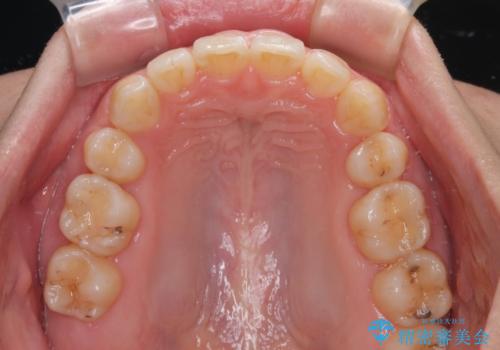

上下の抜歯位置を変えることで、左右ともに理想的な咬み合わせを達成することができました。

横顔の印象はほとんど変わらないものの、唇を閉じたときに前に出ていた下唇が、治療後には少し下がった状態に仕上げることができました。